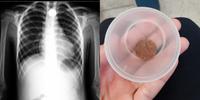

A moeda ficou entalada na garganta do menino por 18 horas e só foi retirada por meio de um procedimento médico

Uma simples brincadeira com uma moeda de cinco centavos terminou no hospital. O menino Miguel Carvalho Moraes, de 8 anos, engoliu a moeda e, somente após cerca de 18 horas com o item entalado na garganta, conseguiu retirar o objeto por meio de um procedimento médico. De acordo com o G1 Santos e Região, o morador de Registro, no interior paulista, foi transferido para um hospital, onde fez uma endoscopia.

Murilo levou o menino para a Unidade de Pronto Atendimento (UPA) da cidade, onde foi constatado, por um exame de raio-X, que a criança estava com a moeda presa na região do pescoço. O menino foi internado e a equipe médica decidiu tentar transferência para outro hospital, já que a unidade não realiza a endoscopia.